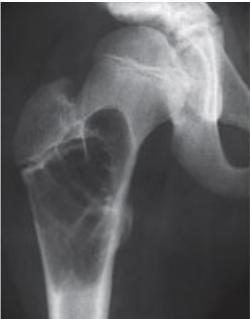

Clinical Example

- 11 year old boy: Pain in left hip